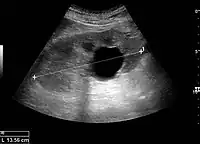

Figure 15. End-stage hydronephrosis with cortical thinning. Measurement of pelvic dilatation on the US image is illustrated by ‘+’ and a dashed line.[1]